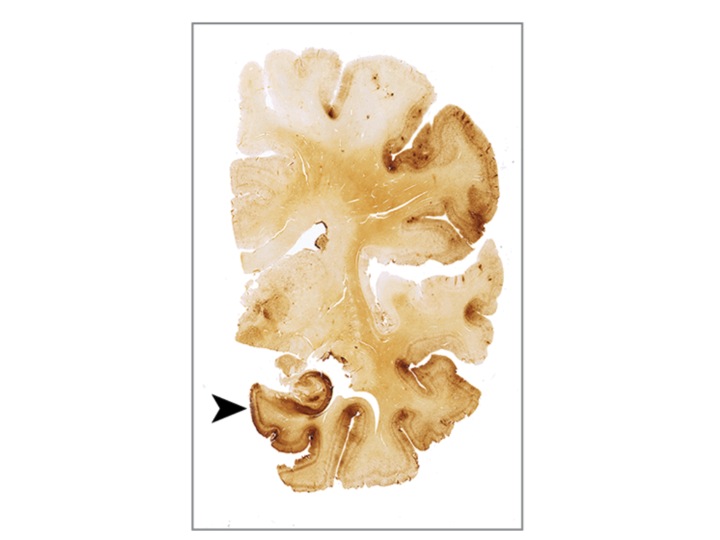

The brains tell the real story, though. Post-mortem brains are analyzed by looking for tell tale signs of brain injury (seen below.) The brain of someone who has CTE looks different under the microscope than a normal brain. The brain trauma creates a destruction of the tissue of the brain, one of the hallmarks of which is a protein called Tau. In the figures below, the presence of Tau is marked by the dark brown color. The more Tau, the worse the symptoms.

There are four stages of CTE. The levels go from mild (I) to severe (IV) can be seen in the figures below. The images on the left are a slice of the whole brain. The image on the right is a magnified (or zoomed in) image of the slice on the left. The pictures below are from the paper released last week in JAMA that analyzed the brains of football players. The stage III and IV brains are from former NFL players.